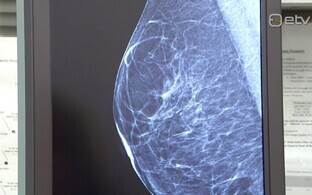

Качественная медицинская помощь становится все более доступной для жителей Эстонии: в Ида-Таллиннской центральной больнице (ITK) открылся специальный Центр здоровья груди, в котором пациенты с жалобами на молочную железу могут пройти быструю диагностику, а в случае обнаружения рака груди – мультидисциплинарное лечение.

Повышенное внимание к заболеваниям молочной железы требует от медицинской системы готовности оказывать высококачественную помощь пациентам с соответствующими проблемами, и для этой цели в ITK создали специальный Центр здоровья груди.